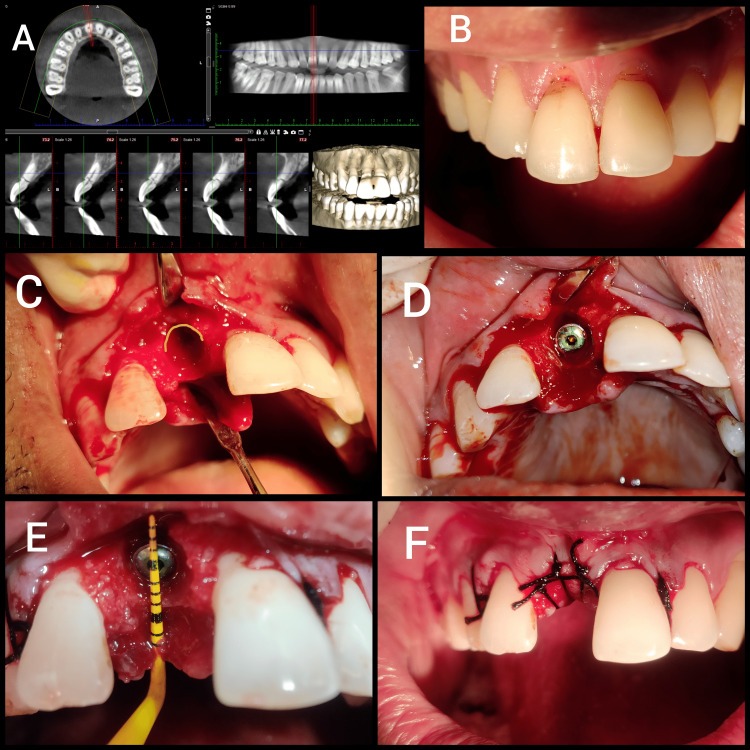

sursa foto: PMC9744434

Socket Shield Technique

Descrisă pentru prima dată de Hürzeler în 2010, socket shield reprezintă cea mai documentată variantă PET și a schimbat modul în care sunt abordate extracțiile în zona estetică. Tehnica presupune păstrarea fragmentului radicular bucal, după separarea și îndepărtarea porțiunii palatine, cu scopul de a menține complexul ligament parodontal-os fasciculat și de a conserva conturul bucal. Investigațiile histologice ale autorilor au arătat că suprafața internă a fragmentului radicular poate forma un strat nou de ciment, fără a inhiba osteointegrarea implantului plasat palatinal.

Indicațiile includ dinți cu fracturi verticale fără patologie pulpară activă, cazuri cu cerințe estetice ridicate sau situații în care păstrarea formei vestibulare este critică. Contraindicațiile menționate în literatură includ rădăcini mobile, absența laminei bucale și prezența infecțiilor active. Datele existente arată că, atunci când fragmentul radicular este stabil și corect preparat, implantul poate fi integrat cu predictibilitate, iar stabilitatea profilului vestibular este superioară celei obținute după extracția completă.